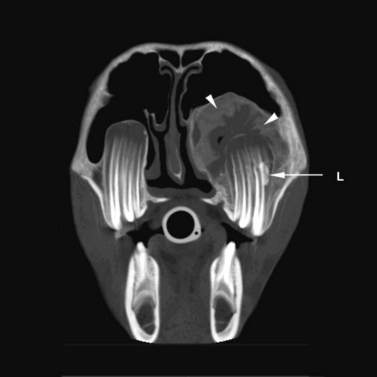

Polydontia

Extra, or supernumerary, teeth may have a normal anatomy or may be misshapen, malformed, and often misplaced (see Ch. 8). Due to their abnormal apical areas, it may be difficult to definitively ascertain if supernumerary teeth are apically infected or not. Quinn et al19 described a ‘domed soft-tissue opacity in the floor of the maxillary sinuses’ dorsal to the apices of supernumerary 12s (Fig. 13.36) to be a relatively consistent finding in affected horses. Supernumerary teeth can easily go unrecognized, particularly if the entire cheek tooth row is not included in the radiograph. Supernumerary cheek teeth are often very long, due to lack of attritional wear, and diastemata may develop between supernumerary and adjacent teeth.

image image image

Fig. 13.36 Polydontia. Supernumerary maxillary cheek teeth (Triadan12s) are the most common supernumerary cheek teeth in horses. The 12 is usually markedly overgrown as in (A) but may be unerupted as in (B) if there is inadequate space (overcrowding). Note the abnormal shape of the apical area of the 112. (C) An example of overgrown bilateral supernumerary mandibular 12s.